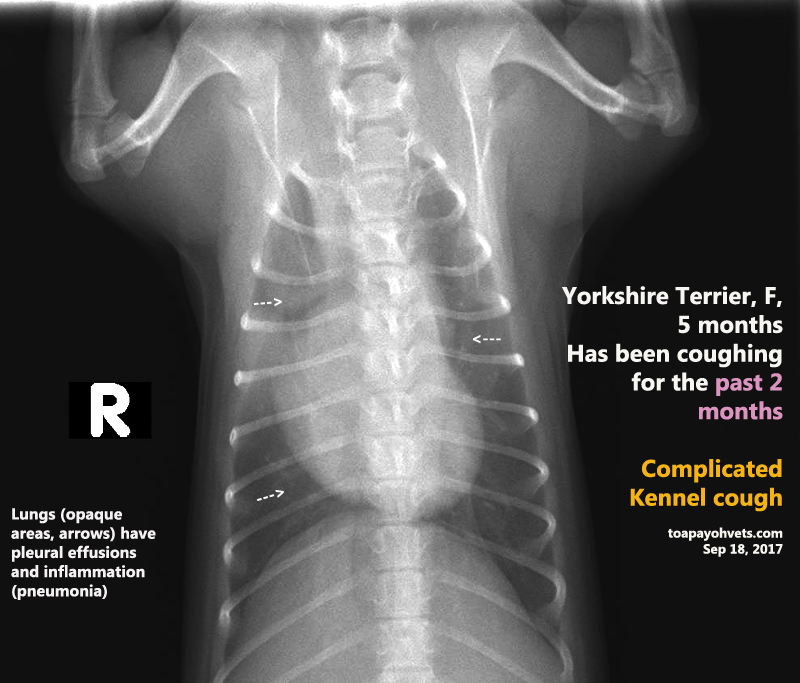

From 2010vets.blogspot.com

Veterinary, Photography and Travel Stories for vet students and pet Kennel Cough Yorkshire Terrier The classic symptom of kennel cough is a persistent, forceful cough. Kennel cough is a highly contagious respiratory infection that can affect dogs of all breeds and sizes, including the beloved yorkshire terrier. Are you noticing your dog has a runny nose and a sudden, harsh cough that sounds like a goose honking? Most of these conditions require veterinary. Kennel. Kennel Cough Yorkshire Terrier.

Veterinary, Photography and Travel Stories for vet students and pet Kennel Cough Yorkshire Terrier The classic symptom of kennel cough is a persistent, forceful cough. Rebecca greenstein, dvm, rover’s veterinary medical advisor, details below some home remedies for kennel cough that are safe for dogs. It often sounds like a goose honk. Most of these conditions require veterinary. Are you noticing your dog has a runny nose and a sudden, harsh cough that sounds. Kennel Cough Yorkshire Terrier.

Veterinary, Photography and Travel Stories for vet students and pet Kennel Cough Yorkshire Terrier Kennel cough is a highly contagious respiratory infection that can affect dogs of all breeds and sizes, including the beloved yorkshire terrier. Most of these conditions require veterinary. There’s a good chance they’re suffering from an upper respiratory. It often sounds like a goose honk. Not only is it highly contagious, but many. Kennel cough is one of the most. Kennel Cough Yorkshire Terrier.

Veterinary, Photography and Travel Stories for vet students and pet Kennel Cough Yorkshire Terrier Are you noticing your dog has a runny nose and a sudden, harsh cough that sounds like a goose honking? Rebecca greenstein, dvm, rover’s veterinary medical advisor, details below some home remedies for kennel cough that are safe for dogs. It often sounds like a goose honk. Not only is it highly contagious, but many. There’s a good chance they’re. Kennel Cough Yorkshire Terrier.

Veterinary, Photography and Travel Stories for vet students and pet Kennel Cough Yorkshire Terrier The classic symptom of kennel cough is a persistent, forceful cough. Learn home remedies and medical treatments to help ease your dog’s kennel cough symptoms and speed up their recovery. Rebecca greenstein, dvm, rover’s veterinary medical advisor, details below some home remedies for kennel cough that are safe for dogs. There’s a good chance they’re suffering from an upper respiratory.. Kennel Cough Yorkshire Terrier.

Veterinary, Photography and Travel Stories for vet students and pet Kennel Cough Yorkshire Terrier The classic symptom of kennel cough is a persistent, forceful cough. Not only is it highly contagious, but many. Most of these conditions require veterinary. It often sounds like a goose honk. Learn home remedies and medical treatments to help ease your dog’s kennel cough symptoms and speed up their recovery. There’s a good chance they’re suffering from an upper. Kennel Cough Yorkshire Terrier.